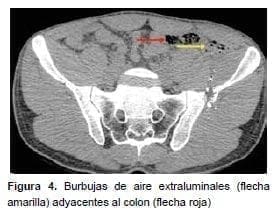

En este mismo grupo de 14 pacientes operados, 12 tuvieron lesiones que requerían manejo quirúrgico; en dos (el 4 y el 8), la laparotomía no fue terapéutica (figuras 4 y 5); en tres, el abdomen no se pudo evaluar, aunque había estabilidad hemodinámica, por lo cual se les practicó TC; el número 1 tenía politrauma, llegó intubado y sedado a la institución, al igual que el número 12; el número 2 tenía trauma raquimedular asociado.